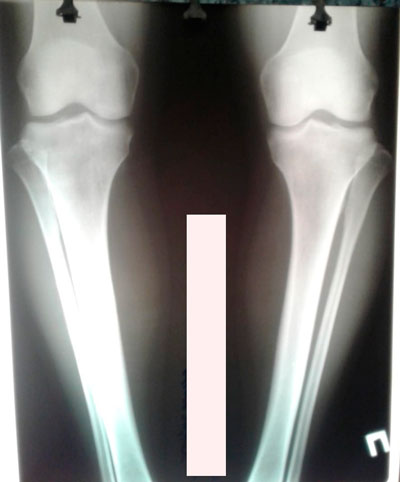

Дата операции - 04.07.2019г.

Дата снятия аппаратов - 10.10.2019г.

Срок сращения - 95 дней.